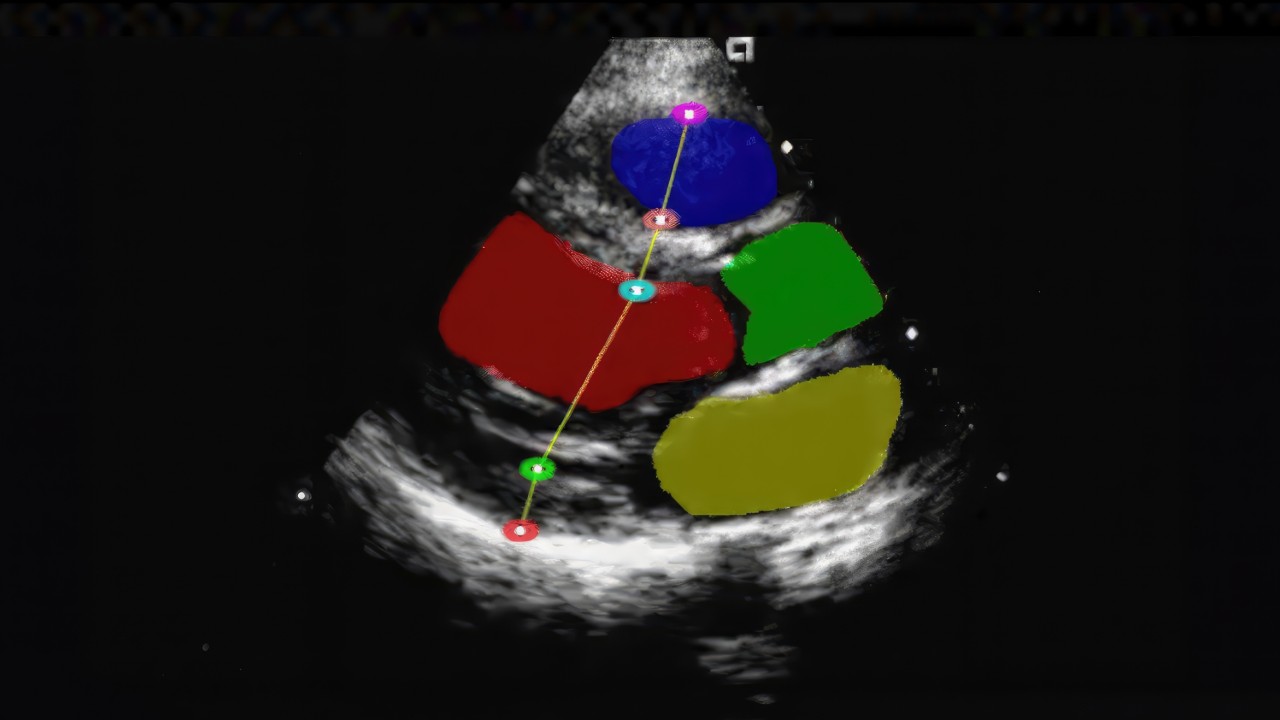

NVIDIA Holoscan Reference Applications and operators provide ready-to-use, customizable examples and components for building real-time, AI-enhanced sensor processing applications.

Medical device and AI developers looking to accelerate their development can use Holoscan Reference Applications to quickly build and deploy solutions across medical imaging, sensor processing, and edge computing.

Holoscan reference applications significantly reduce development time and complexity, leveraging diverse contributions from both NVIDIA and its partner ecosystem to bring a diverse collection of workflows and operators to its open repository.